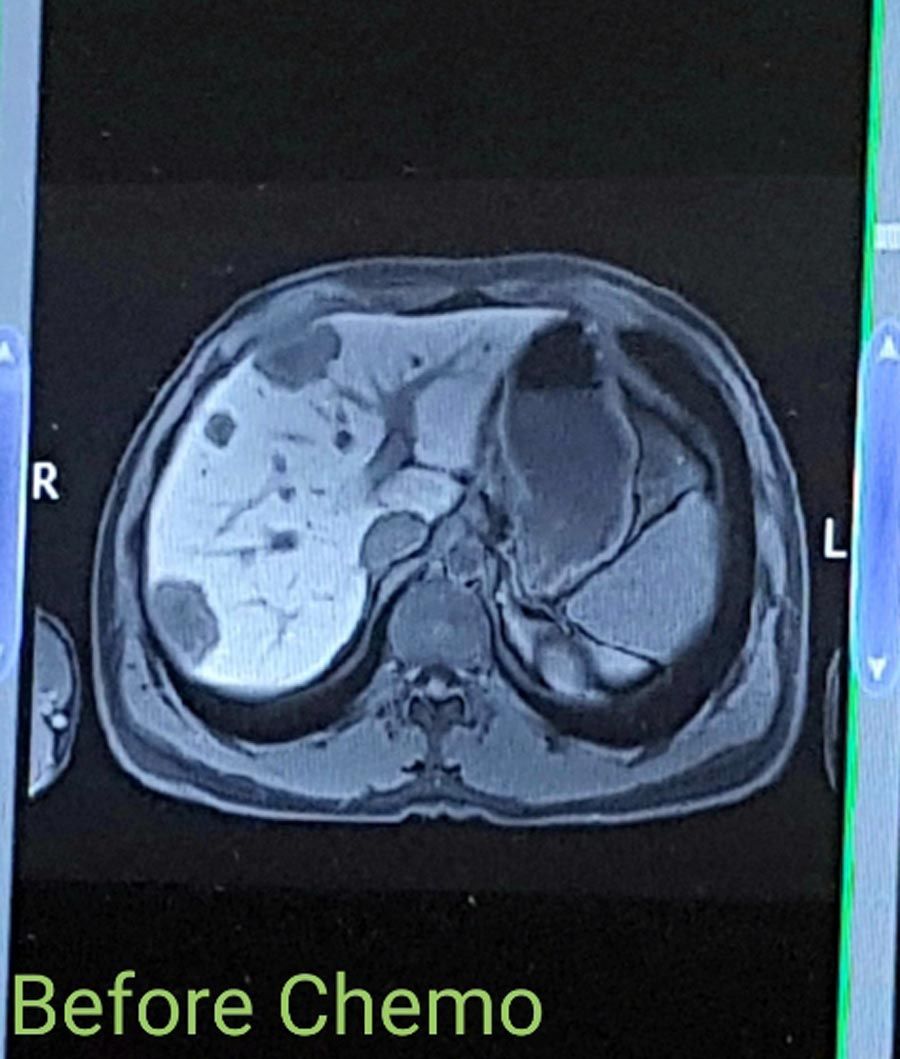

Initially, it seemed that the tumors in his liver were inoperable, and doctors explained that he would need to undergo chemotherapy to see if they shrank – in which case, surgery could be possible.

In January, he started five rounds of chemotherapy over three months, meaning he had to give up work while Carlie progressed with the pregnancy, doing her best to keep calm and not get stressed.

“Chemo completely wiped me out. But, at the end of the three months, I was rescanned and it had done its job."

“The tumors in my liver had reduced enough for doctors to be able to operate."